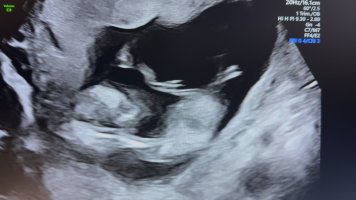

Veldig vanskelig NUB, men tipper jente.En vennine sin, noen som vil gjette![]()

Serbiske NuB dessverre